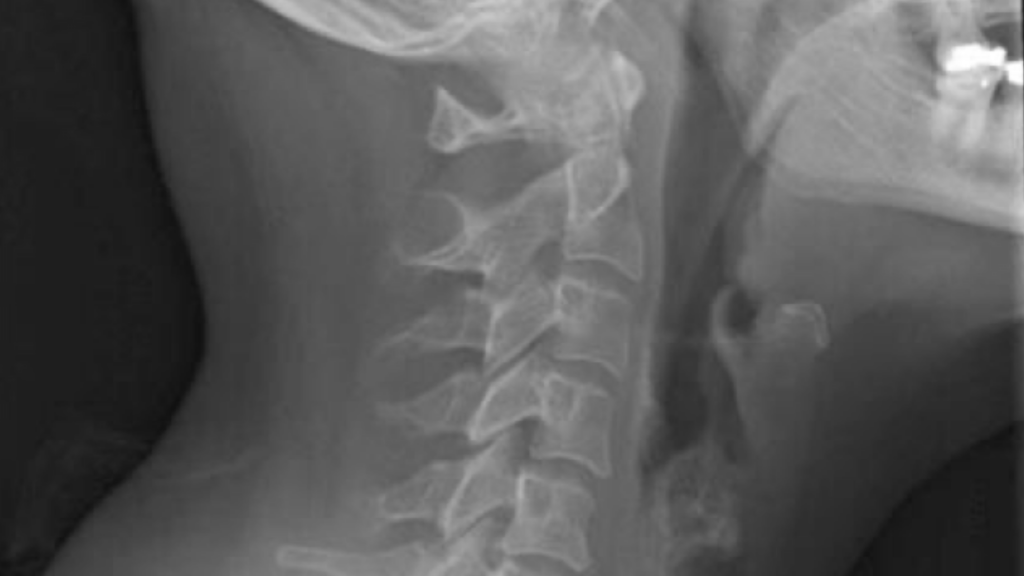

At Hampstead Chiropractic Office, we utilize “state of the art” procedures to diagnose your condition, including Orthopedic and Nerve evaluations, X-Ray, Computerized Postural, and Range of Motion Testing and Muscle Strength Evaluation. When appropriate, Dr. Shields refers to and consults with medical specialists to ensure his patients are diagnosed correctly.